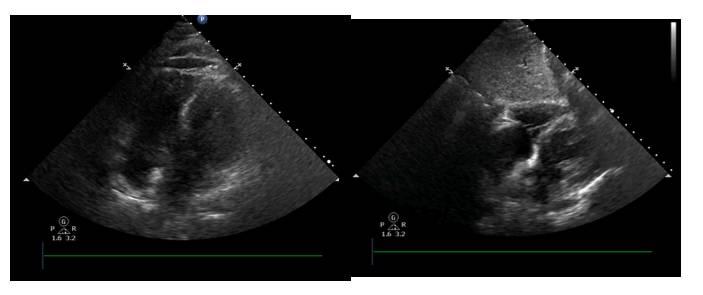

体循环淤血改善

循环有所改善

♥去甲肾上腺素:0.4ug—0.09ug/kg/min

♥乳酸:正常范围

♥心脏舒缩功能好转,循环灌注改善(无酸中毒,乳酸正常)